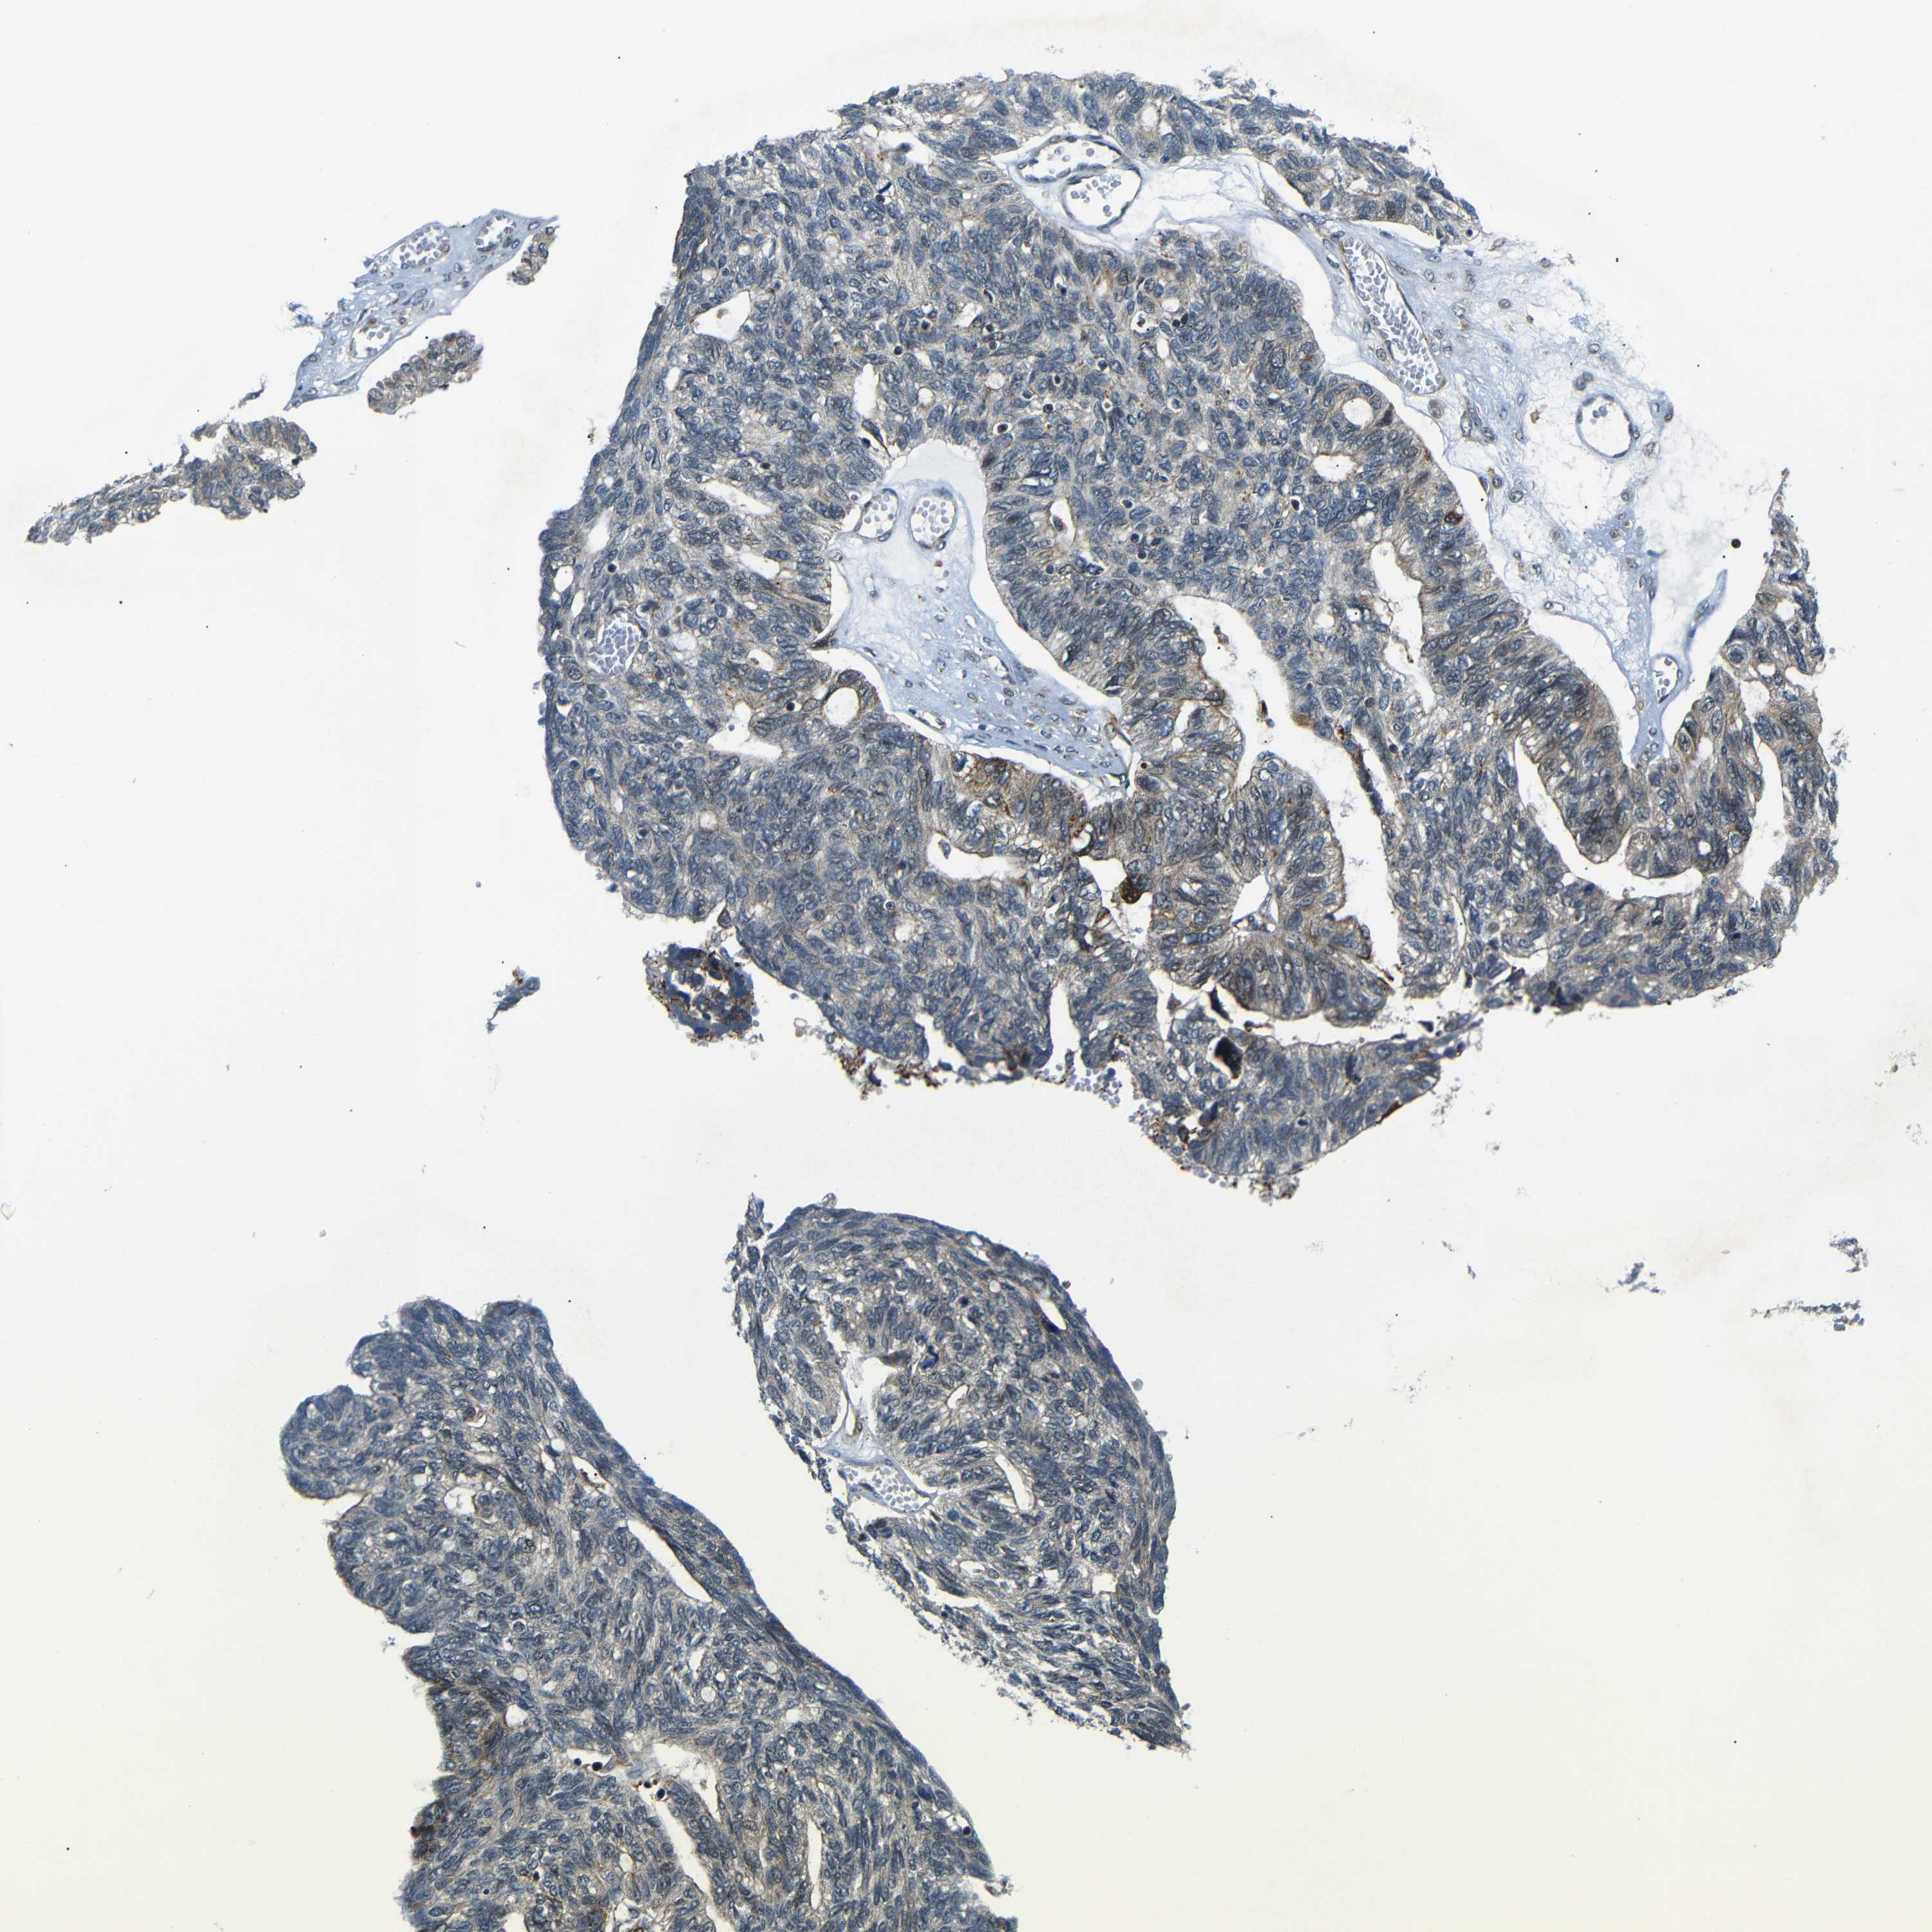

OVARIAN CANCER - Protein expressioni

A mouse-over function shows sample information and annotation data. Click on an image to view it in a full screen mode. Samples can be filtered based on level of antibody staining by selecting one or several of the following categories: high, medium, low and not detected. The assay and annotation is described here.

Note that samples used for immunohistochemistry by the Human Protein Atlas do not correspond to samples in the TCGA dataset.

Antibody stainingi

Antibody staining in the annotated cell types in the current human tissue is reported as not detected, low, medium, or high, based on conventional immunohistochemistry profiling in selected tissues. This score is based on the combination of the staining intensity and fraction of stained cells.

Each image is clickable and will lead to virtual microscopy that enables deeper exploration of all samples and also displays staining intensity scores, fraction scores and subcellular localization as well as patient and tissue information for each sample.

Antibody HPA013328

Staining

High

Medium

Low

Not detected

Intensity

Strong

Moderate

Weak

Negative

Quantity

>75%

75%-25%

<25%

None

Location

Nuclear

Cytoplasmic/membranous

Cytoplasmic/membranous,nuclear

Cystadenocarcinoma, serous, NOS

Carcinoma, endometroid

Cystadenocarcinoma, mucinous, NOS

Carcinoma, NOS